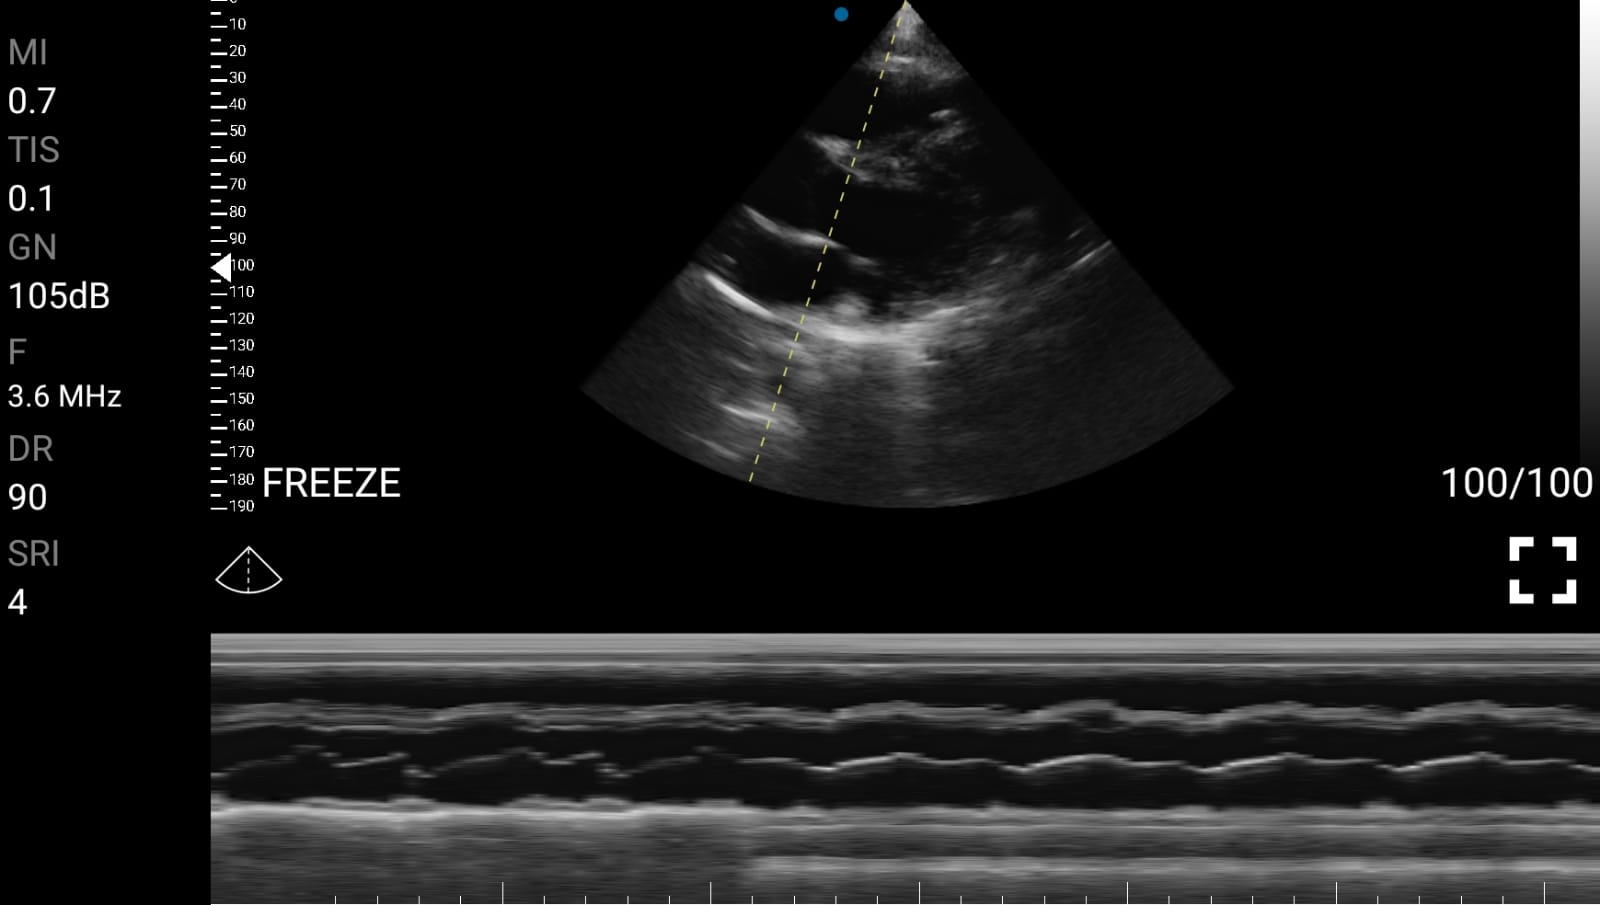

• Ejection Fraction (EF): Εκτίμηση του κλάσματος εξώθησης της αριστερής κοιλίας.

• Πάχος μυοκαρδίου και υπερτροφία: Για διάγνωση υπερτροφικής μυοκαρδιοπάθειας.

Παραδείγματα

Ολες οι παραπάνω απεικονιστικές εξετάσεις έχουν ληφθεί από φορητή συσκευή όπως: Apple Iphone, Tablet, Samsung Mobile Phones και διάφορες άλλες φορητές συσκευές.